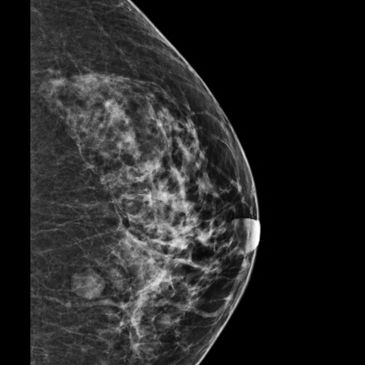

Principle. Low-dose x-ray of compressed breast (DM); DBT acquires multiple low-dose projections to reconstruct thin slices, reducing tissue overlap.